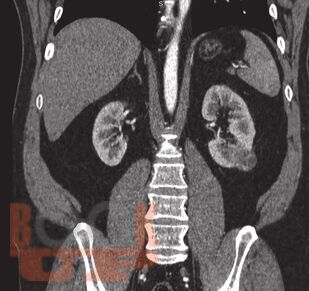

Трехтроакарная лапароскопическая резекция почки

В данном учебном пособии представлены сведения по анатомии и физиологии почек, эпидемиологии, этиологии, патогенезу, клинике, диагностике и современному хирургическому лапароскопическому лечению опухолей почек.